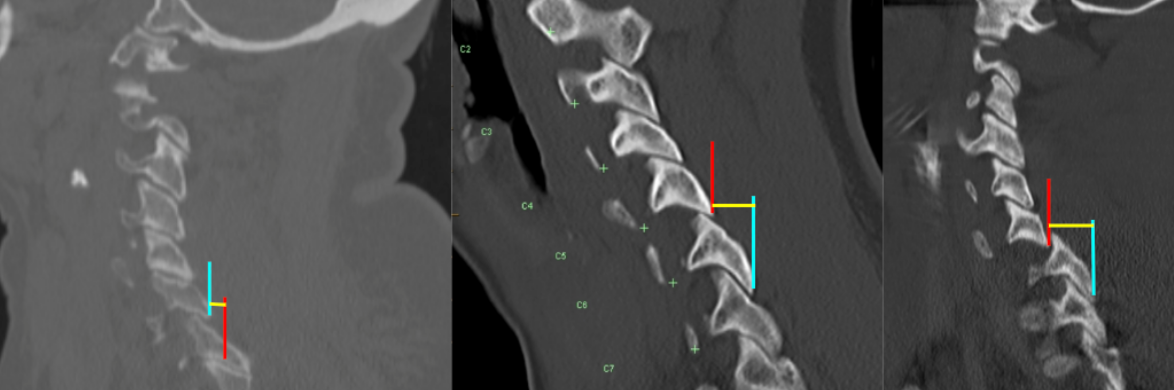

Image Type Cervical Spine X-Ray CT Scan MRI Scan Atlantodental Interval (ADI) Basion–Axial Interval (BAI) Basion–Dens Interval (BDI) Canal Occupying Ratio (COR) Clivo-Axial Angle Facet Joint Overlap (Percent Overlap Method) Facet Joint Step-Off/Dislocation Grabb-Oakes Measurement (pB - C2 line) Occipital Condyle–C1 Interval (CCI) Posterior Atlantodental Interval (PADI) Power’s Ratio Sagittal Vertical Axis (SVA) Segmental Angle Translation on Sagittal Reconstruction